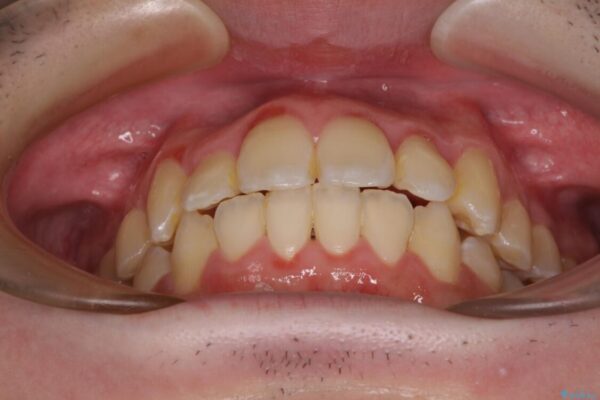

シザーズバイトは強く咬合する奥歯を移動させるため、多くの場合においてワイヤー矯正の装置のみでは改善が困難となります。

奥歯の咬み合わせ改善は治療初期からしっかりとアプローチする必要があるため、補助装置を積極的に利用します。

治療途中